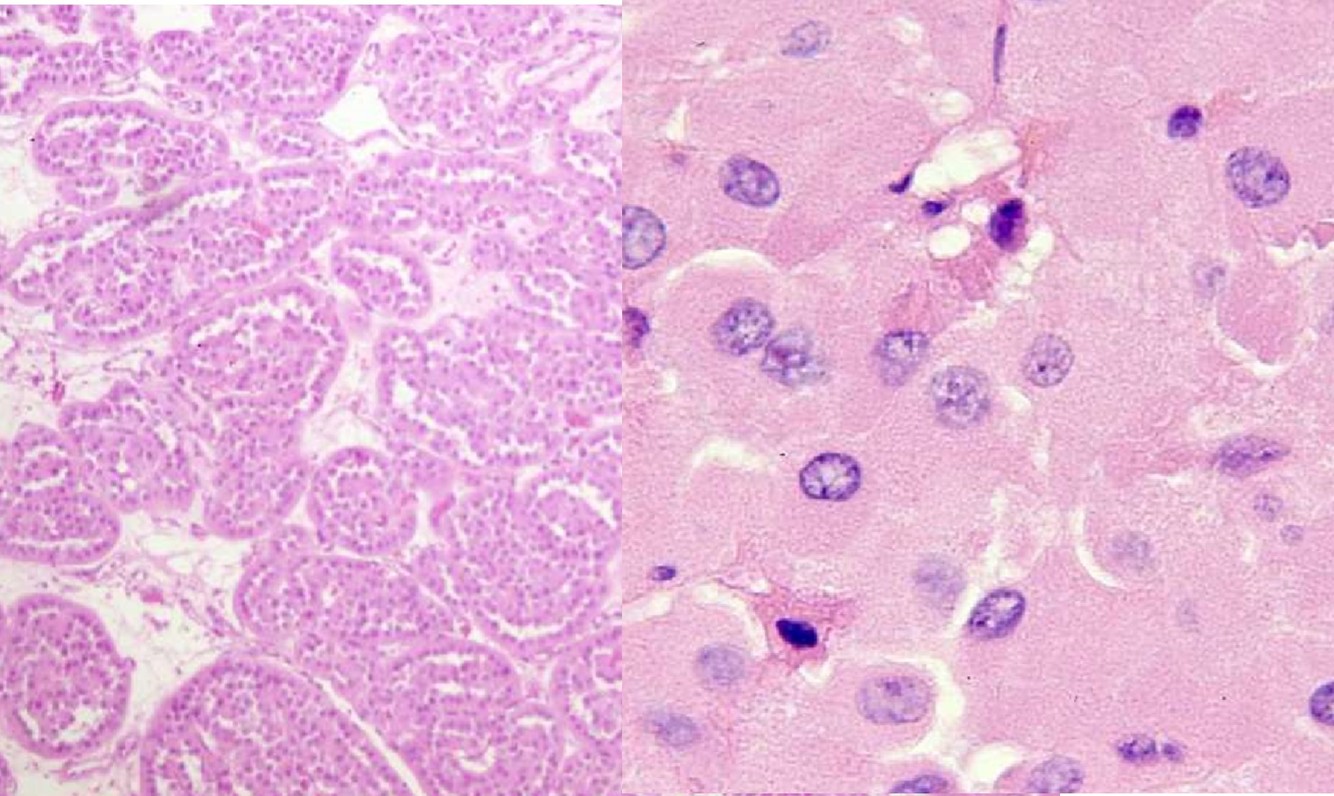

CYSTIC NEPHROMA

- Presents as a multilocular renal cyst

- Bimodal in age distribution: children less than 4 years of age, young women

- Excellent prognosis

MULTILOCULAR CYSTIC RCC

- Presents as a multilocular renal cyst

- Excellent prognosis; classified by the WHO as a neoplasm of low-malignant potential